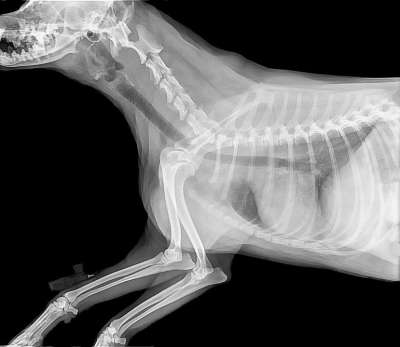

您现在的位置是:首页 > 动物图 > 兽医图 分类:自然图狮子图老虎图宠物图狗图猫图鸟图 标签:转换器组长英国短发霜霉病啄木鸟喝水比尔奶油乳酪土豆奶酪地球苹果豆瓣菜旱金莲猫伤心Gebrigsschweisshund巴伐利亚州黑色的信羽毛旧信非洲场景赛车狗Belvie的头发在风格玛丽莲美丽的金发女郎格拉德斯通Eurasier黑面罩古遗址昏昏欲睡的小猫金迪奥别尔乔绿色看颜色的小鹿狮子对Albenga热带稀树草原模糊的背景看着鸟桌子底下坐狗前阳台程序员在家办公雀鹰状自制生锈的尾巴炉子一个靠垫女祭司尖叫鸡畦犁沟婊子蓝色海岸红Ur 猫 小猫 动物 宠物 兽医 毛皮 猫 小猫 雄猫 严肃 兽 动物 休息 宠物 兽医 毛皮 药品 兽医 设备 耳检查 狗 关心 医生 感染 耳朵 疥疮 海滩 人体内的水 海 沙 兽医 狗 狗的海滩 雪纳瑞 微型雪纳瑞 鼻子 牙齿 解剖学 狗 兽医 Caudalansicht 上颚 兽医 审查的狗 救护车 诊所 宠物 狗 健康 预防 动物 诊断 脑 解剖学 狗 生物学 背 身体 兽医 大脑 小脑 科学 小狗 宠物 卡通片 画画 狗窝 兽医 犬科动物 盒 造影 骨 医疗的 图片 图像 兽医 狗 动物 造影 兽医 兽医 诊所 狗 病人 动物 犬类 欣慰的 关心 药品 医疗的 鼻子 牙齿 解剖学 狗 兽医 Rostralansicht 上颚 猫 小猫 动物 宠物 兽医 毛皮 狗 可爱的 宠物 犬类 动物 实验室 拉布拉多犬 医疗保健 兽医 兽医 宠物 专业 医生 动物 狗 猫 小猫 动物 宠物 兽医 毛皮 职业教育和培训 医生 狗 小狗 犬类 兽医 医疗服务 检查心脏 猫 基蒂 兽医 宠物 猫科动物 动物 国内的 毛皮 橙色的 猫 衣领 绝育 玳瑁 宠物 动物 猫科动物 国内的 兽医 小猫 头 解剖学 狗 矢状切面 鼻腔 口腔 脑 兽医 生物学 科学 兽医 数字 猫 乐趣 可爱的 家猫 动物 亲爱的 家畜 人物 兽医 血压 压力测量 心电图 记录 心 心脏检查 药品 心脏疾病 脑 解剖学 狗 Paerparat 马 生物学 背 身体 兽医 狗 肖像 宠物 小狗 犬类 幽默 动物 兽医 友谊 可爱的 狗 兽医 听诊器 关心 12下一页尾页